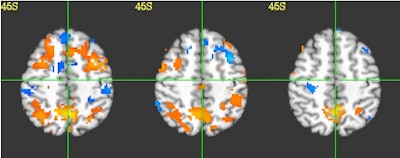

![]() |

| Functional MRI images of a high school football player with functionally observed impairment in the absence of a diagnosed concussion showed significant reductions of fMRI activity in the frontal lobe from preseason (left) to in-season (middle and right). Orange region denotes greater activity for the two-back test compared to the one-back, compared to the blue region, which shows less activity. |

Specifically, the most consistent impairments in changes in the fMRI activation were a decrease in activity in the posterior temporal lobe, which resulted in the athletes having impaired language and memory. Among the four control subjects, the analysis found no consistent changes in their fMRI brain activation.

"The players who are showing this impairment were experiencing an appreciably greater number of hits to the head than the other players who showed no impairment," Talavage said. "In particular, they showed a significantly larger number of blows to the top front of the head and forehead area."